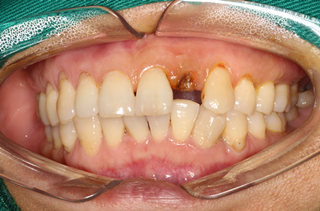

家住深圳的邓女士是一家个体户老板,年轻时忙着做生意,对牙齿的清洁也疏忽,甚至牙齿有了蛀牙之后也无暇去看医生,再加上平时牙齿卫生也不注意保持,前一段时间邓女士龋坏的牙齿渐渐脱落,剩下的只有牙齿残根。

牙齿的缺失很不巧的是正好是门牙的部位,非常影响形象,跟人交谈都不敢开口大笑,吃东西的时候还总是卡在牙缝东西,清洁非常不易,加上最近一段时间,由于牙齿缺失,旁边的牙齿缺少倚靠,邓女士觉得门牙都开始松动,听朋友说到种植牙是牙齿缺失最好的修复方式,看到麦芽的活动并充分了解了之后决心重新修复自己的牙齿。

牙齿拔除之后